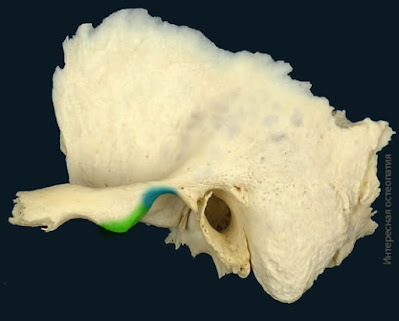

Различают две крайние формы бугорка: низкий и широкий бугорок соответствует плоской нижнечелюстной ямке, высокий и узкий - глубокой ямке (рис. 1-25).

Рис. 1-25. Форма суставного бугорка:

а - плоская; б - средневыпуклая; в - крутая